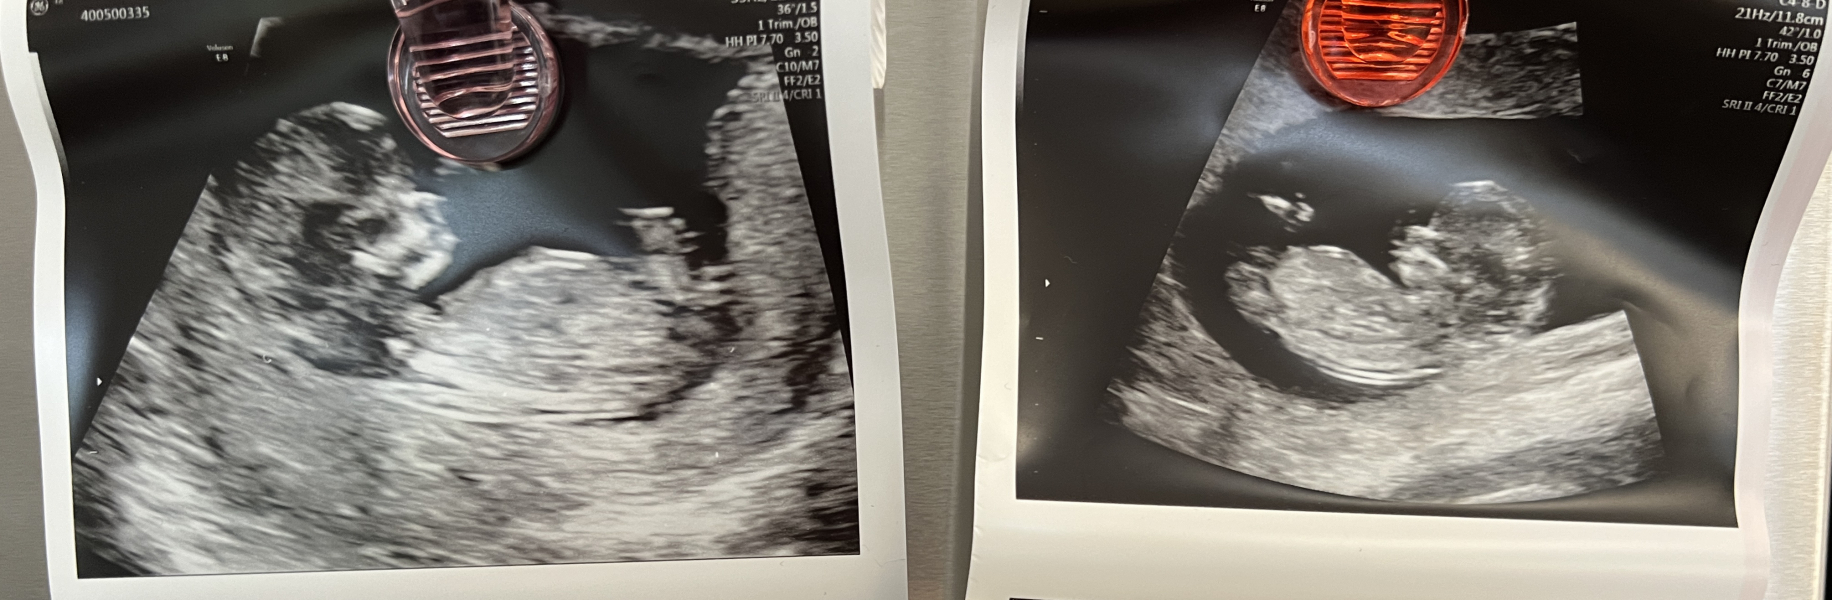

Hope everyone is doing ok! The exhaustion is relentless with twins so trying to take it as easy as I can with a toddler in tow. Thankfully the nausea seems to be easing up. We've booked an early gender scan for four weeks time, so exciting. Our official 12 week NHS scan went well last week and it felt incredibly special and surreal seeing the two babies next to each other! ❤️

WickWood · 07/04/2024 16:00

For anyone wondering about discharge!